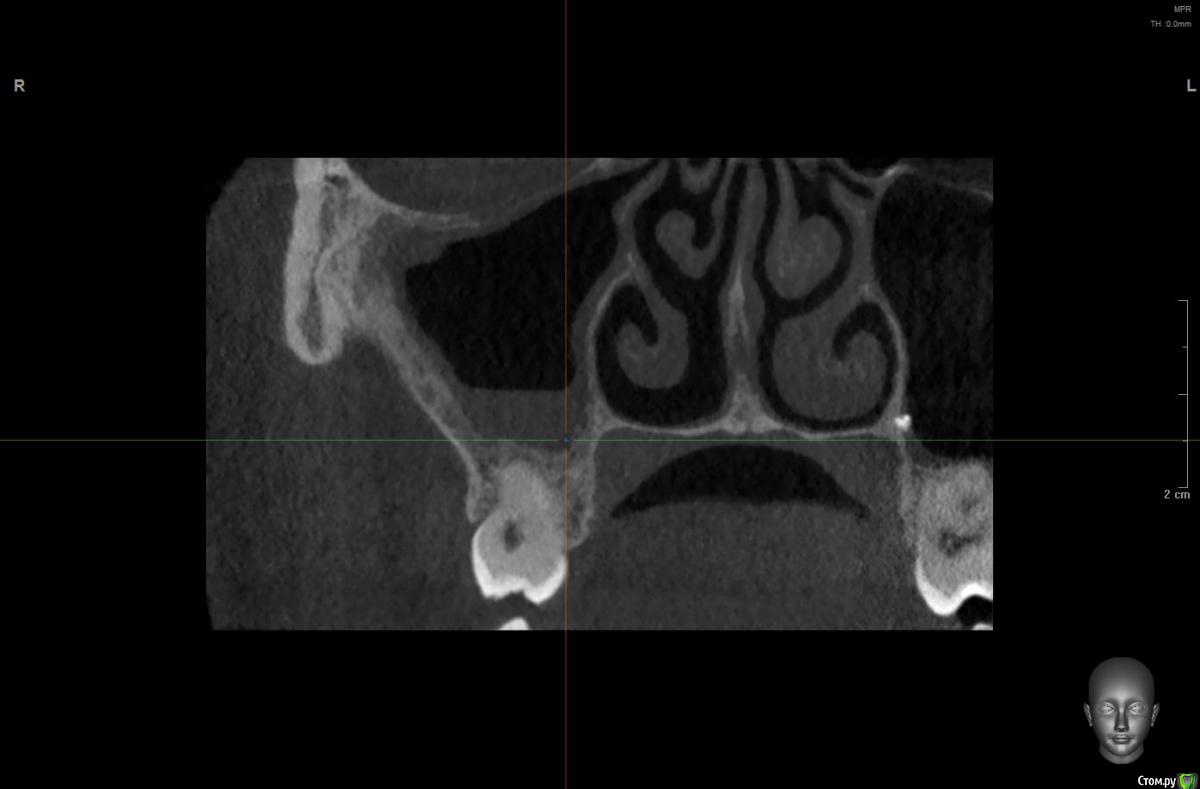

wladdX Опубликовано 30 июня, 2020 Поделиться Опубликовано 30 июня, 2020 Несколько скриншотов из КЛКТ 2 Ссылка на комментарий

колесников Опубликовано 30 июня, 2020 Поделиться Опубликовано 30 июня, 2020 Есть жидкость в пазухе на момент снимка. Можно только предполагать что является причиной воспаления,полной картины нет. Возможно это рельеф дна пазухи. В области 6ки углубление,где как в колодце застаивается слизь и прочее что попадает в полость и естественного дренажа не происходит. Я бы рекомендовал поставить 2 импланта 5,6. В области 6го провести закрытый синуслифтинг. Рельеф дна пазухи выровняется и вероятно обострений больше не будет. По крайней мере процессы происходящие в пазухе никак не повлияют на имплантацию,тогда как имплантация может купировать процессы в пазухе. Ссылка на комментарий

Оvzaika Опубликовано 1 июля, 2020 Автор Поделиться Опубликовано 1 июля, 2020 Несколько скриншотов из КЛКТ 25_1.jpg25_2.jpg26_1.jpg26_2.jpgH_M.jpgСпасибо! Ссылка на комментарий